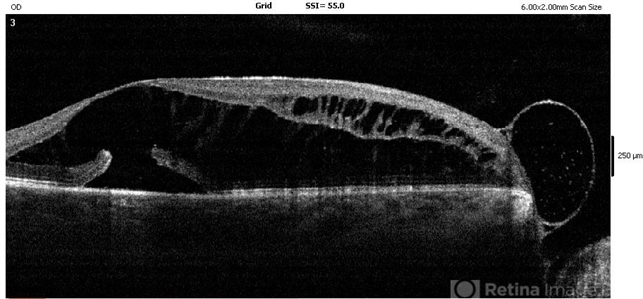

- optic disc pit, optical coherence tomography (OCT)

- OCT of a patient with optic disc pit.